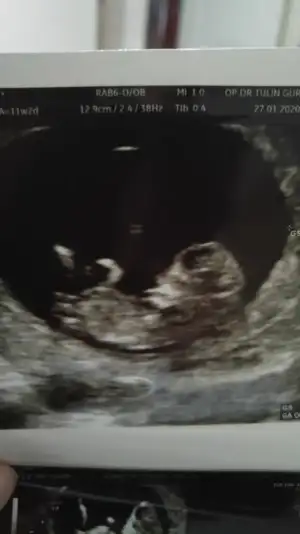

Teşekkürler uc tane usg var şuan elimde bgnun paylaşıyorum hemen, heyecanla yorumunuzu bekliyorum 😊😊😊💕

• 20200127_195653_HDR.webp

20200127_195653_HDR.webp

11,6 KB · Görüntüleme: 39

• 20200127_195645_HDR.webp

20200127_195645_HDR.webp

13,7 KB · Görüntüleme: 34

• 20200127_195456_HDR.webp

20200127_195456_HDR.webp

12,4 KB · Görüntüleme: 33

Evet ilk hayırlısıyla 12 de tekrar paylasicam bakalim degisiklik olucak mi 😊 hislerim erkek yonunde isteğimse kız kısmet artık